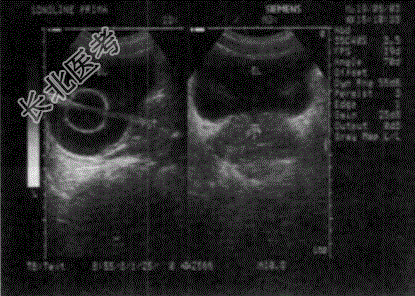

- 单项选择题如图,膀胱内出现的异常回声, 以下最可能的诊断为   (   )

A、膀胱憩室

B、膀胱内囊肿

C、膀胱血块

D、导尿管

E、膀胱肿瘤